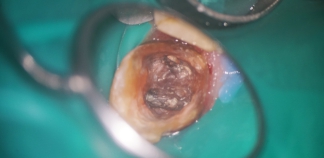

До лечения

Жалобы на постоянную ноющую боль.

Пациенту 33 года.

Как лечили

Распломбирован и обработан корневой канал. Пролечен периодонтит, зуб закрыт временной пломбой.

Финишная ирригация, закрытие корневого канала пломбой. Зуб подготовлен под временную коронку.

Лечение проведено в течение двух недель.